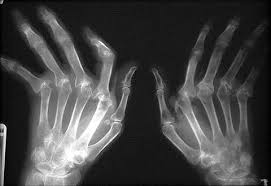

Hoy es DIA INTERNACIONAL DE LA ARTRITIS REUMATOIDE

DIA INTERNACIONAL DE LA ARTRITIS REUMATOIDE

Más de 70 millones de personas en el mundo sufren de esta enfermedad que afecta más a las mujeres que a los hombres entre los 35 y 60 años de edad.

La artritis reumatoide (AR) es una enfermedad articular crónica degenerativa, incurable, cuyo origen no está definido y es más frecuente en mujeres; afecta principalmente las articulaciones, por lo que el padecimiento puede ocasionar discapacidad y al mismo tiempo una disminución en la productividad laboral e invalidez del paciente.

Entre las 200 variantes de las enfermedades reumáticas que afectan actualmente a cerca de 14 millones de mexicanos se encuentran la artritis crónica juvenil (niños y adolescentes), y la artritis reumatoide en adultos. La AR genera inflamación de articulaciones que persisten por años y causan daños irreversibles en cartílagos, huesos, tendones y ligamentos. Se calcula que en México hay cerca de 1 millón de personas con esta enfermedad.

Estudios realizados a nivel internacional, la artritis reumatoide es la principal causa de incapacidad y uno de los problemas médicos más frecuentes a nivel mundial i. Debido a este panorama, en el marco del Día Mundial de la Artritis Reumatoide, especialistas hacen un llamado a la población para sensibilizar sobre la importancia de tener un diagnóstico y tratamiento oportuno del padecimiento, afirmando son indispensables para detener la progresión de la enfermedad, la que conduce a la pérdida de movimiento, disminución en la capacidad para trabajar, mayores costos médicos y genera la necesidad de cirugía.

“Al menor síntoma y sospecha de artritis reumatoide debe de acudirse con el médico especialista, quien prevendrá cualquier alteración que afecte la vida de los pacientes y familiares”, Es una enfermedad autoinmune, es decir, el sistema inmunológico ataca a sus propias células y tejidos sanos, y aunque su causa exacta es desconocida, los investigadores creen que pueden contribuir factores hereditarios.

Cuando un paciente vive con artritis reumatoide, éste se enfrenta a un impacto social y económico; sin embargo, a pesar de que se conocen estas afectaciones no siempre son contempladas en el paciente, por lo que la enfermedad evoluciona cambiando radicalmente su calidad de vida y la de su familia.

Actualmente no se ha reconocido alguna cura para este padecimiento, no obstante la mejor posibilidad de reducir el impacto de esta enfermedad sobre el estilo de vida reside en comenzar a tratarla desde etapas tempranas mediante un programa individualizado y planeado cuidadosamente por el médico reumatólogo y otros profesionales de la salud.

Existen diferentes tratamientos para esta enfermedad. Hasta hace 10 años se contaba con medicamentos que mejoraban de leve a moderadamente los síntomas, sin embargo con el paso del tiempo la enfermedad seguía evolucionando. Es así que el desarrollo de nuevas terapias que impidieran este desarrollo era fundamental. Hoy en día, se cuentan con tratamientos biológicos, que bloquean las moléculas encargadas de producir inflamación y destrucción articular, frenando la progresión de la enfermedad y brindando mejoría en la calidad de vida de los pacientes y previniendo deformidades articulares y por ende la discapacidad.